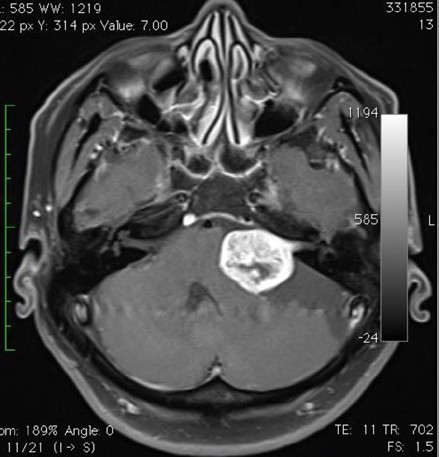

聽覺神經瘤(Acoustic Neuroma)又稱為聽神經許旺氏細胞瘤(Schwannoma),或前庭神經鞘瘤(Vestibular Schwannoma),是許旺氏細胞瘤沿第8條腦神經線生長所致。聽覺神經瘤佔了所有顱內腫瘤(Brain Tumour)總數約8%。不過在區域性劃分上,聽覺神經瘤在小腦腦橋角(Cerebral - pontine Angle)是常見的腫瘤,大約佔了所有小腦腦橋角區域腫瘤(Cerebral-pontine Angle Tumor)的80至90%。